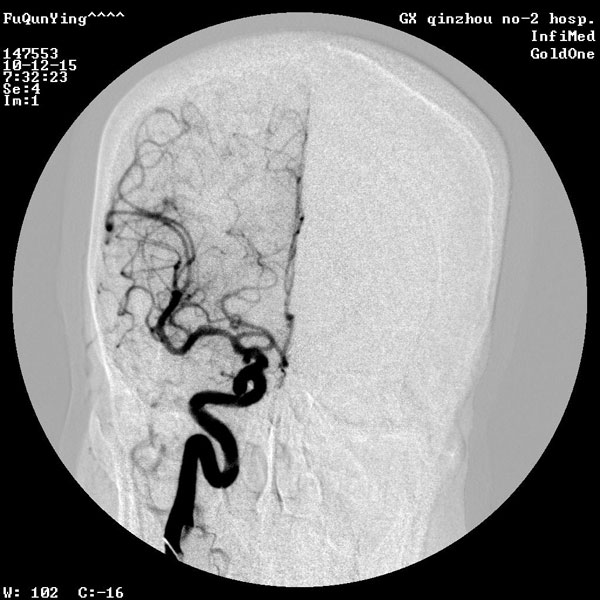

脑血管数字减影造影技术

脑血管数字减影造影 (DSA)是检查脑血管病的最有效方法,不但能清楚地显示颈内动脉、椎基底动脉、颅内大血管及大脑半球的血管图像,还可测定动脉的血流量,所以,目前已被应用于脑血管病检查,特别是对于动脉瘤、动静脉畸形等定性定位诊断。其不但能提供病变的确切部位,而且对病变的范围及严重程度亦可清楚地了解,为手术提供较可靠的客观依据。另外,对于缺血性脑血管病,也有较高的诊断价值。DSA可清楚地显示动脉管腔狭窄、闭塞、侧支循环建立情况等,对于脑出血、蛛网膜下腔出血,可进一步查明导致出血的病因,如动脉瘤、动静脉畸形、动静脉瘘等。

脑血管造影术是检查脑血管病的最有效方法之一。它是通过将含碘造影剂注入到颈内动脉或椎动脉,使脑血管显影,来了解脑血管本身的形态和病变,以及病变的性质和范围。这项检查对诊断脑血管病具有特殊价值。